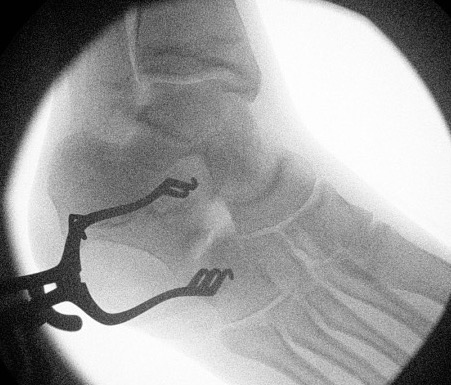

Resection

- resect 1cm of bone with osteotomes

- check with on table oblique intra-operative image

- interpose fat / EDB / bone wax into defect

- K wire to stabilize calcaneocuboid joint